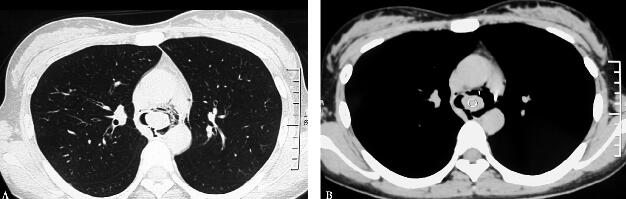

补充上述病史资料后,诊断思路逐渐清晰,患者气道内有阻塞因素,是异物附着在气管壁上?还是气管内肿物?需要进一步做胸部CT检查。胸部3D CT结果显示在隆突上方主气管内生长一肿物(图1A肺窗、B纵隔窗;图2A矢状位、B冠状位),左侧有蒂。因此解释了患者的临床症状特点,右侧卧位时,肿物下坠,将气管完全阻塞,造成患者窒息。左侧卧位时肿物与支气管右侧壁间留有缝隙,使呼吸困难稍有缓解。当气流通过狭窄的气管缝隙时产生哮鸣音,出现喘息症状。并随着肿物的增长,症状日趋严重。继而行纤维支气管镜检查,在隆突上方有圆形结节样肿物几乎将气管完全阻塞(图3),因肿物位置较高,未做活检,活检取材可能因创面出血导致窒息危及生命。

图1

图2